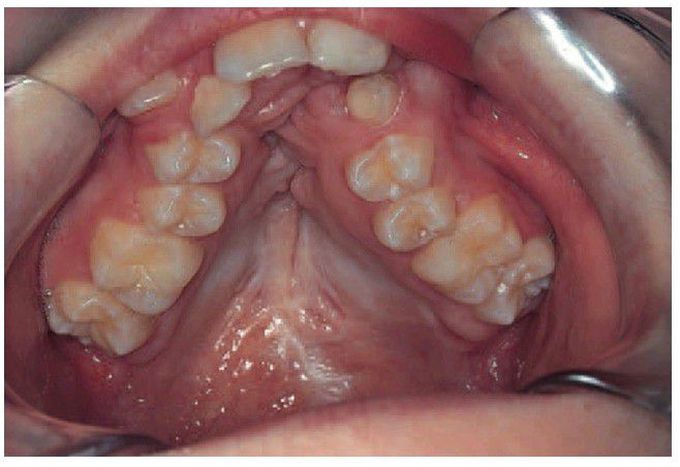

Distorted and narrow maxilla

Collapsed maxilla resulting from traditional surgical repair of cleft palate. Scarring and growth disturbance produce a distorted narrow maxilla. (By kind permission of Mrs E Horrocks.)